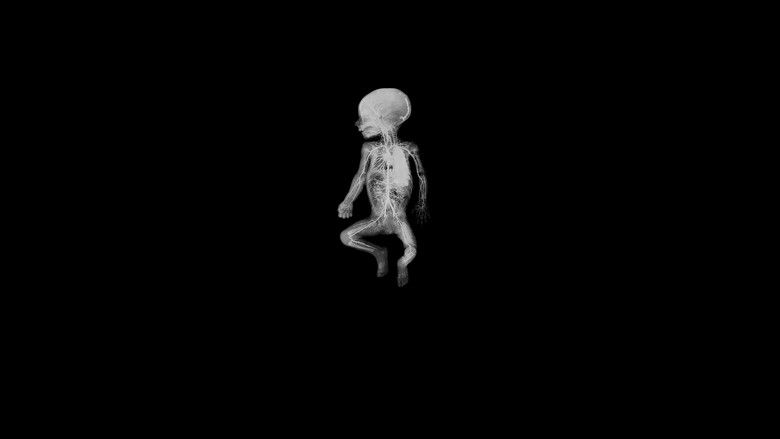

De humani corporis fabrica  документальный

Необыкновенное приключение по внутренностям человеческого тела; или открытие инопланетного ландшафта невиданной красоты.